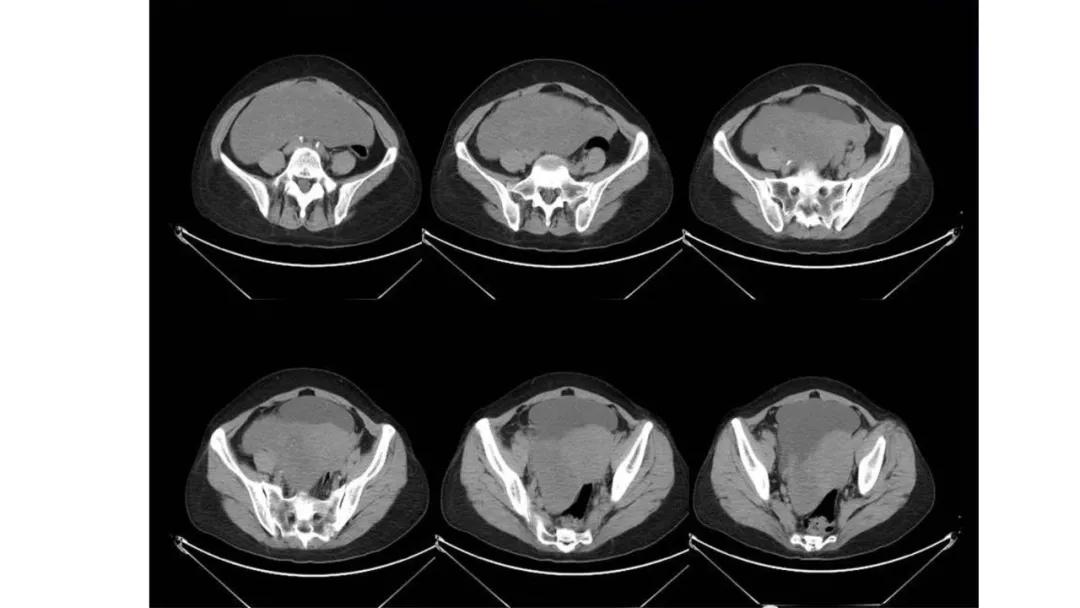

病例10

女,39 岁,体检发现盆腔肿块1月余

CA125:51U/ml

病理:左侧卵巢卵泡膜-纤维瘤